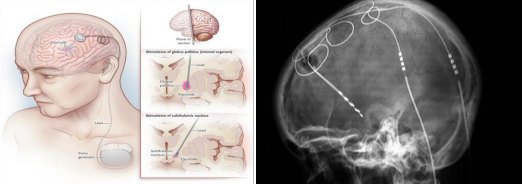

脑深部刺激术(deep brain stimulation, DBS)是将电极植入到患者脑内,运用脉冲发生器刺激其大脑深部的某些神经核,纠正异常的大脑电环路,从而减轻这些神经功能障碍、减少药物治疗剂量。主要用于以帕金森病为代表的运动障碍性疾病,改善肌张力障碍,可明显症状,提升患者生活质量。DBS手术与永久性的不可调节和不可逆的损伤大脑的一些治疗方法(烧灼或放疗)不同,DBS并不破坏大脑结构,可以允许今后的进一步治疗。

DBS手术适应症:

疗效明确的疾病

1、帕金森病:(1)诊断明确,四大症状中至少有两个症状,且一定有震颤或僵直;(2)症状明显,为中度或重度帕金森病,停药时病情≥Ⅲ期;(3)即使加大帕金森病药物治疗剂量,效果仍不满意;(4)有明显药物毒性作用,如“开-关”现象和异动症等;(5)药物副作用大,不能耐受。

2、特发性震颤: 症状明显,药物治疗效果差,影响到工作和生活。

3、肌张力障碍性疾病: 症状明显,药物治疗效果差,影响到工作和生活。

4、意识障碍的促醒治疗。